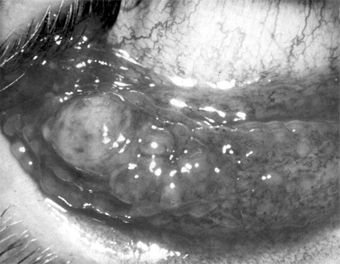

This is a group of conjunctival diseases, usually unilateral, characterized by low-grade fever, grossly visible preauricular adenopathy, and one or more conjunctival granulomas (Figure 5-25). The commonest cause is cat-scratch disease, but there are many other causes, including Mycobacterium tuberculosis, Treponema pallidum, Francisella tularensis, Pasteurella (Yersinia) pseudotuberculosis, Chlamydia trachomatis serotypes L1, L2, and L3, and Coccidioides immitis.

Figure 5-25

Figure 5-25: Conjunctival granuloma. (Courtesy of P Thygeson.)